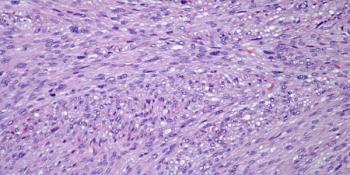

A 27-year-old man presents with a mass in the right calf. A biopsy is performed. What is your diagnosis?